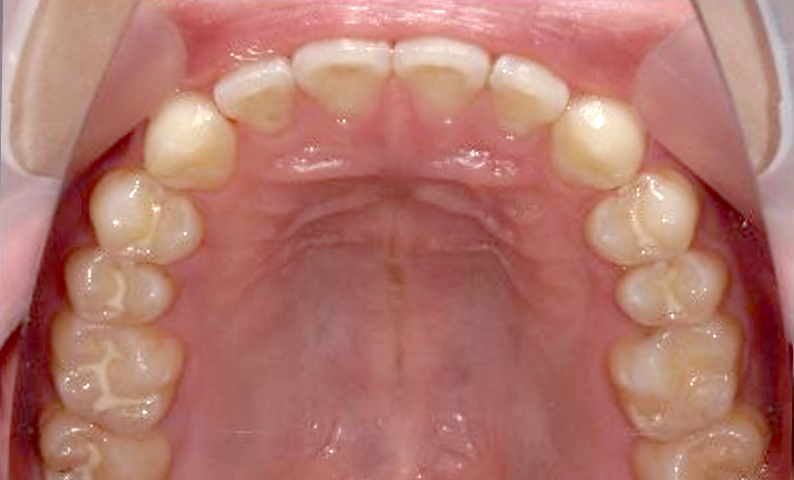

| 治療前 | 治療後 |

|---|---|

|